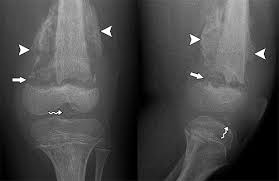

Determination Of Epiphyseal Union Age In The Knee And Hand Joints Bones  Among The Saudi Population In Taif City - Aljuaid - 2018 - Radiology  Research And Practice - Wiley Online Library

Determination Of Epiphyseal Union Age In The Knee And Hand Joints Bones Among The Saudi Population In Taif City – Aljuaid – 2018 – Radiology Research And Practice – Wiley Online Library